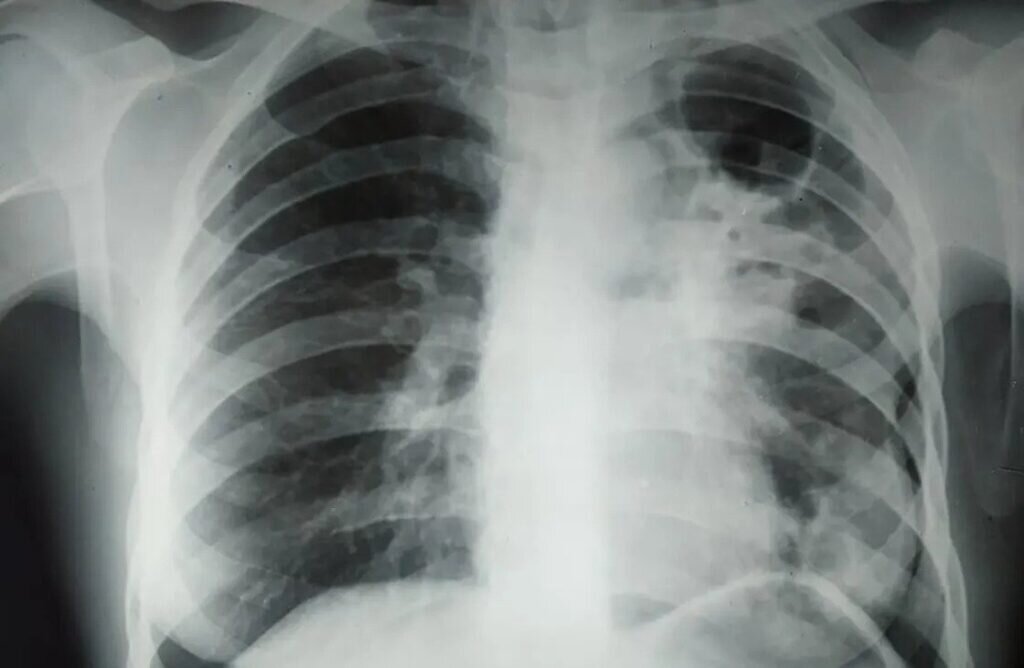

Туберкулез обычно обнаруживают с помощью флюорографии, но на самом деле палочка Коха может присутствовать в нашем организме и в скрытой форме / © ovsalud.org